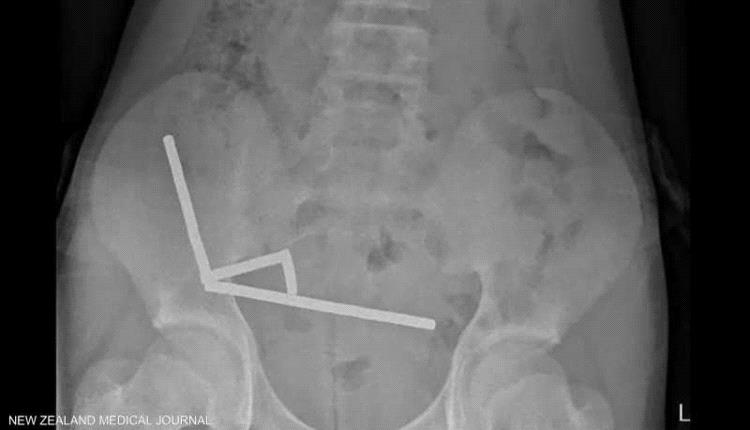

وأظهرت الأشعة أن المغناطيسات تكتلت معا في 4 خطوط مستقيمة داخل أمعاء المراهق، و"يبدو أنها كانت في أجزاء منفصلة من الأمعاء ملتصقة ببعضها البعض بسبب القوى المغناطيسية"، وفق الأطباء.